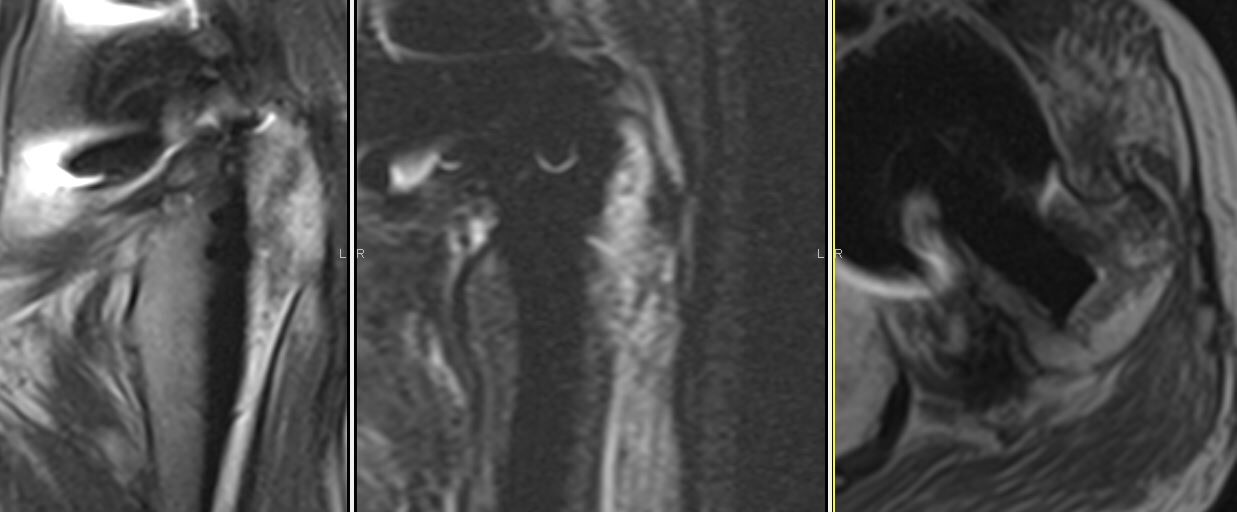

えっ、人工関節が入っているのにMRIを撮像するの?!という声が上がってきそうです。たしかに、人工関節がハレーションになって、周囲の情報は得られないイメージがあります。

しかし、実際には上記のような画像になります。少し分かりにくいですが、左大転子の骨折もしくは骨挫傷を確認できました。

しかも、インプラントはブラックアウトするだけで、CTのように周囲に線状のハレーションが発生することもありません。

何度かご紹介しているように、私は人工関節後の患者さんにも積極的にMRIを施行しています。人工関節後の感染疑い症例も、関節内に液体が貯留しているか一目瞭然に分かります。

人工関節、脊椎インストゥルメンテーション、骨折手術のプレート、髄内釘であっても、チタン合金であるかぎり、MRIは有用だと思います。